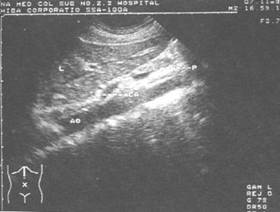

肝*腹主动脉纵切超声显像图——肝(L) 贲门(CA) 胰腺(P) 腹主动脉(AO)